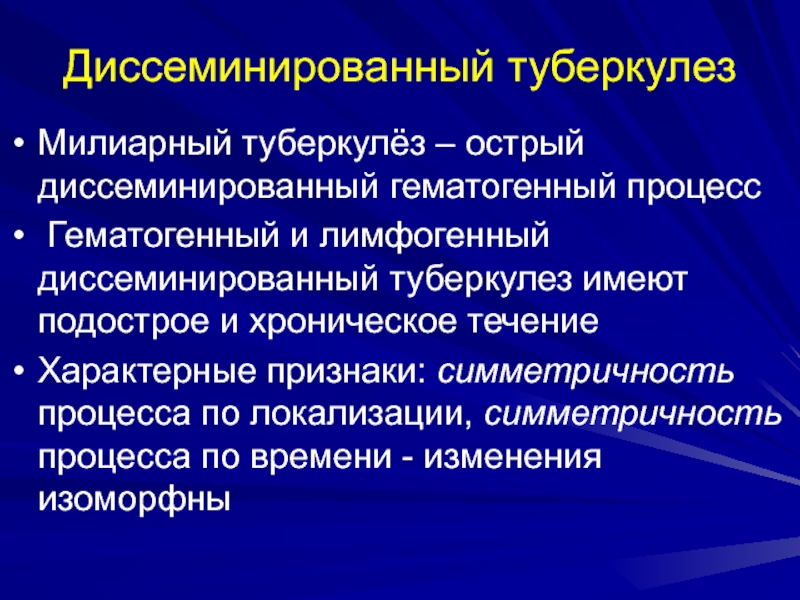

В клинической картине острого гематогенно диссеминированного туберкулеза преобладает